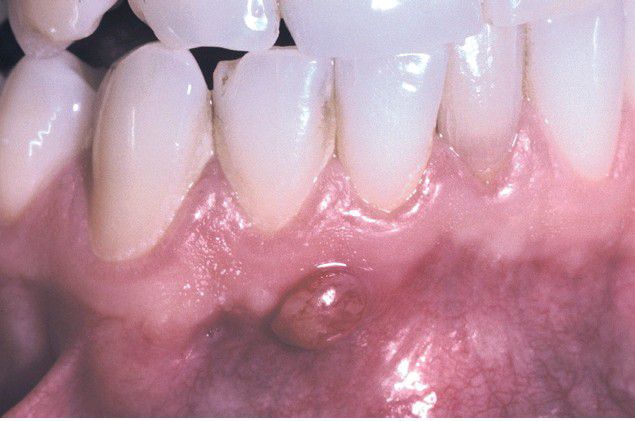

Parulis

. Asymptomatic yellow-red nodule of the anterior mandibular alveolar mucosa. The adjacent teeth were asymptomatic and appeared clinically normal.